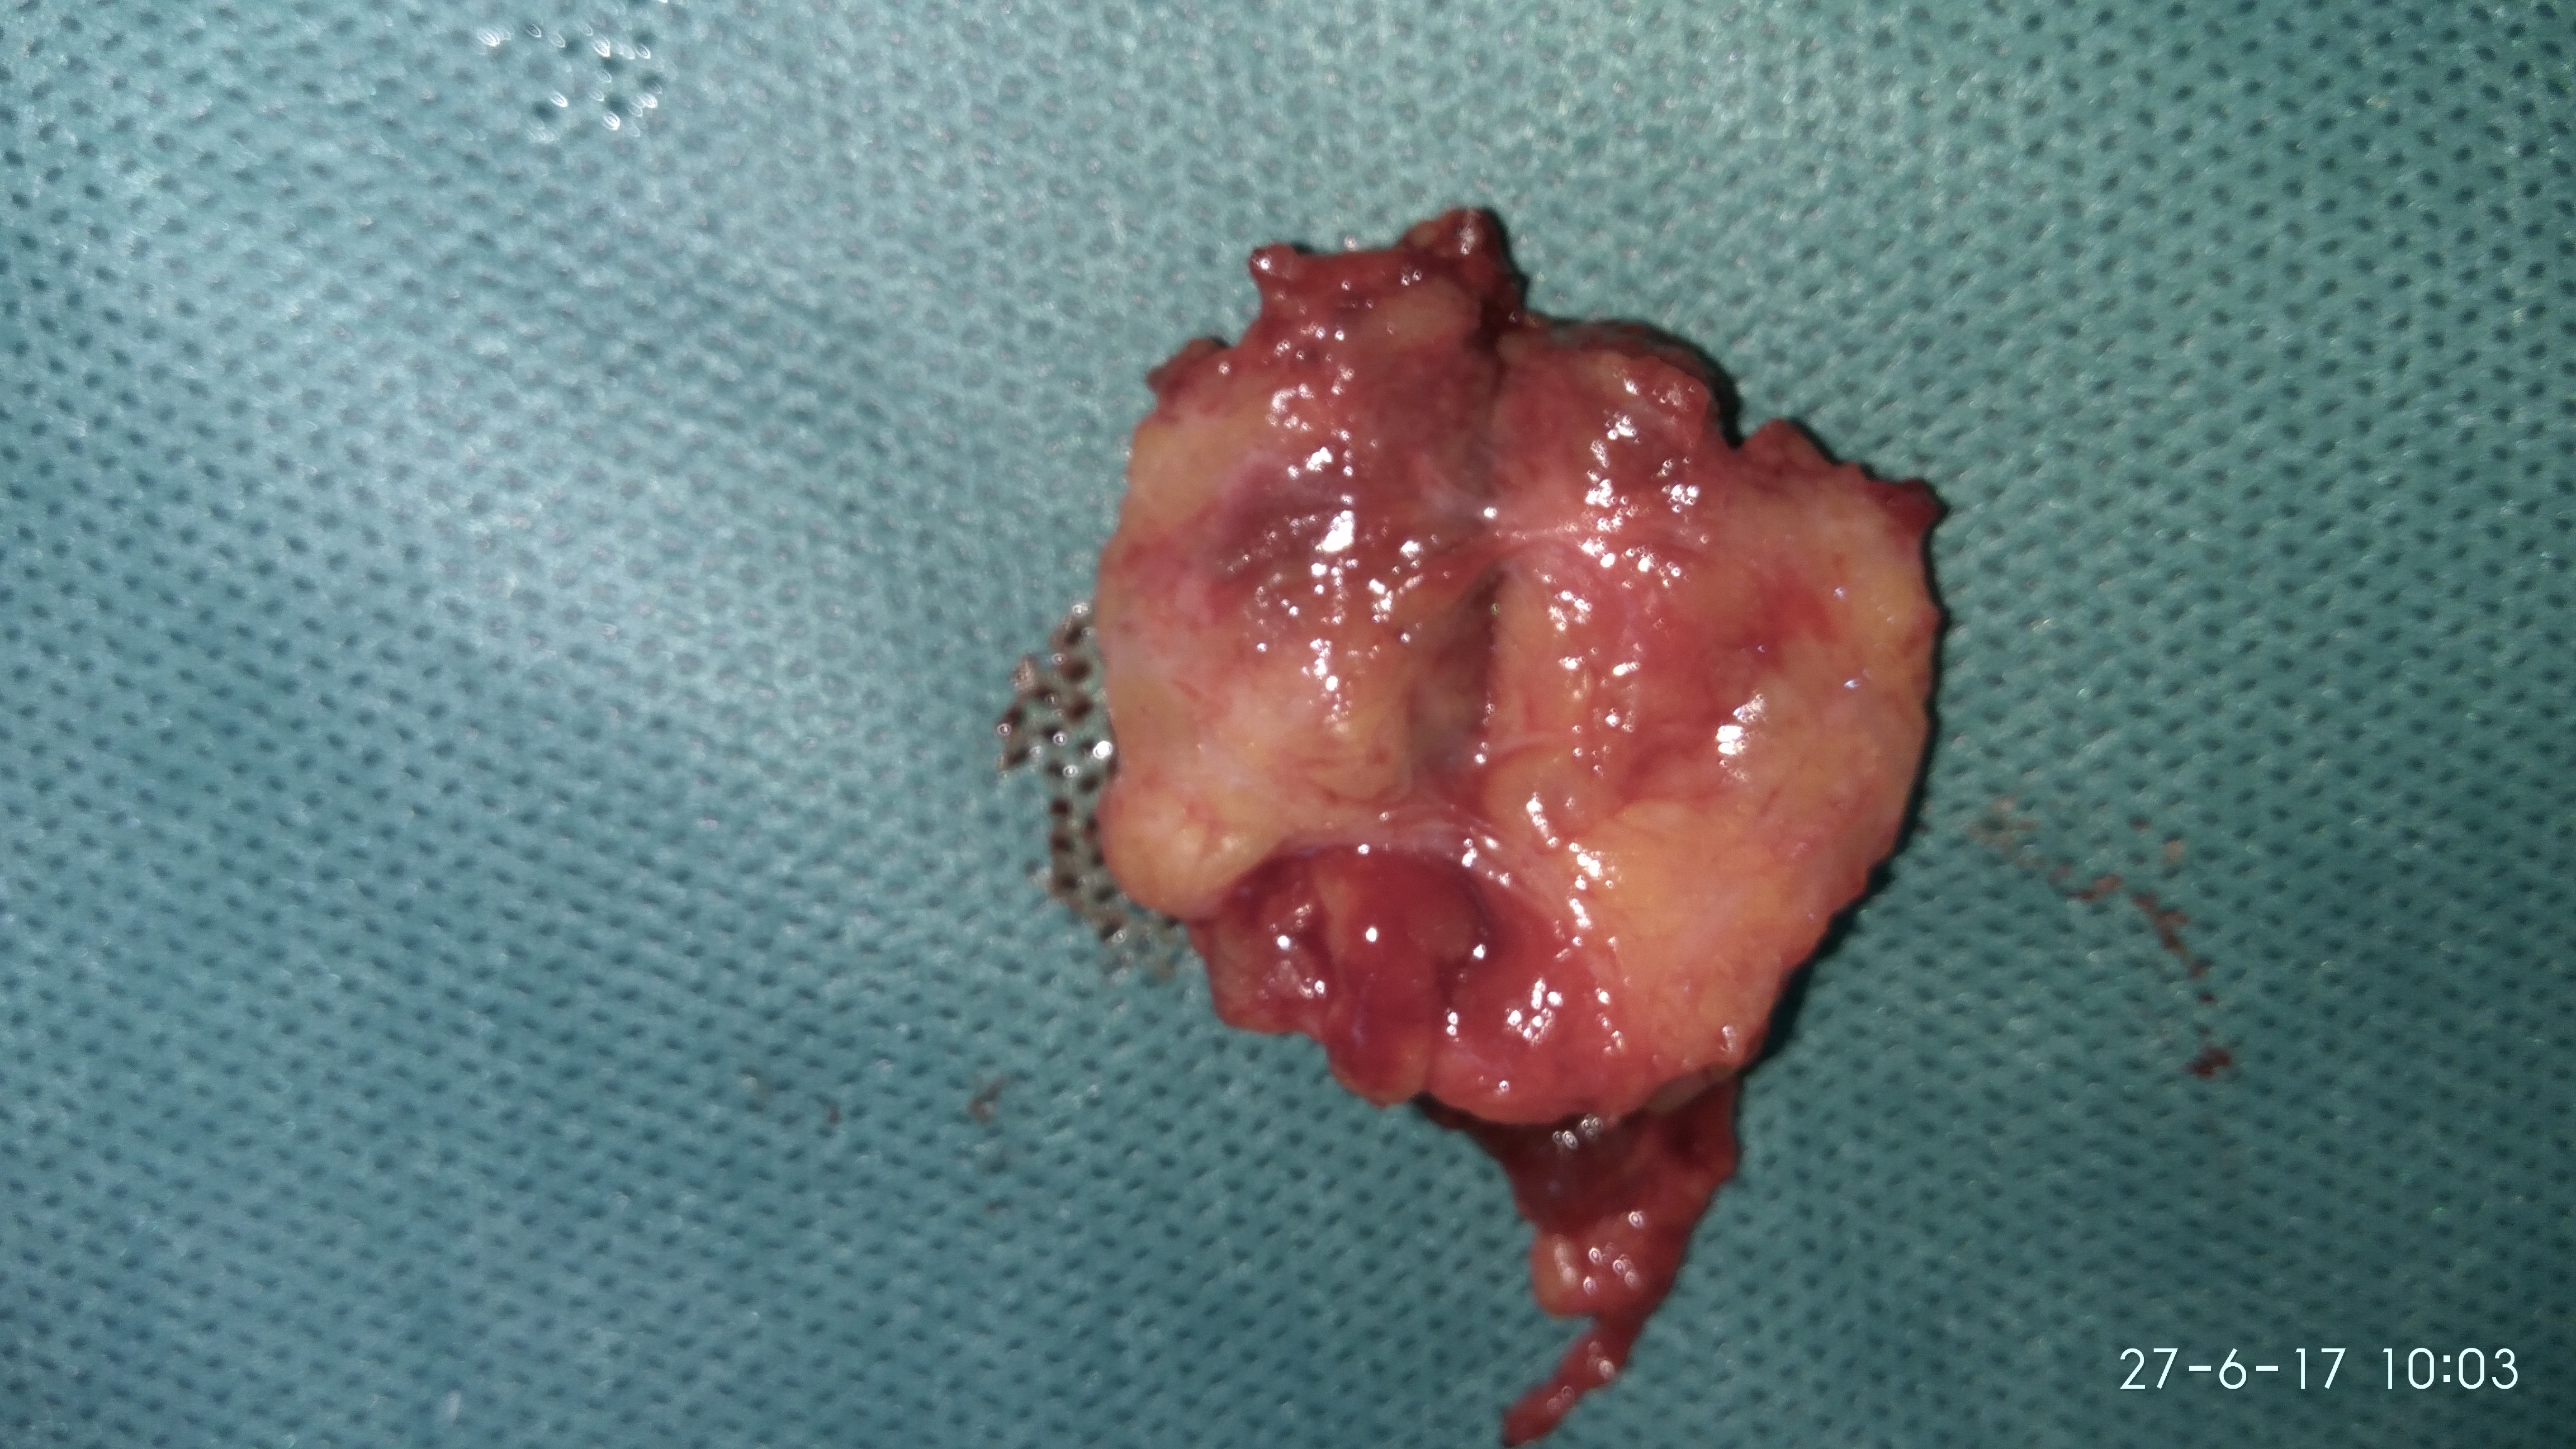

Gross examination of the excised cyst reveals a smooth surface lining of uniform thickness without papillary projections (Courtesy Dr. V. Penopoulos)